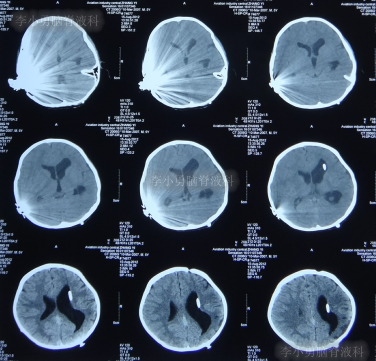

在利奈唑胺、头孢吡肟、利福平等药物抗炎治疗2周后,发热症状逐渐得到控制,意识也开始转清醒,但患儿自己示意有头痛症状;因腰穿未能抽出脑脊液,所以给予甘露醇处理,之后头痛可有缓解。在住院11天时即2012年5月27日(图-4)和住院14天时即2012年6月1日(图-5),分别进行过脑CT的检查,显示脑室有逐渐扩大的表现,但因为病情有所缓解,所以给以继续密切观察的处理。

图-4:2012年5月27日脑CT脑室稍扩大

图-5:2012年6月1日脑CT脑室稍扩大

但是在住院第19天即在2012年6月6日时(注:即在人工耳蜗植入术颅内感染并发症21天时),患儿出现了左眼闭合和右侧肢体瘫痪即交叉性偏瘫,以及进食无力和不能交流的病情加重的表现,立即脑CT检查发现了脑积水的表现(图-6)。

图-6:2012年6月6日脑CT脑室扩大显著